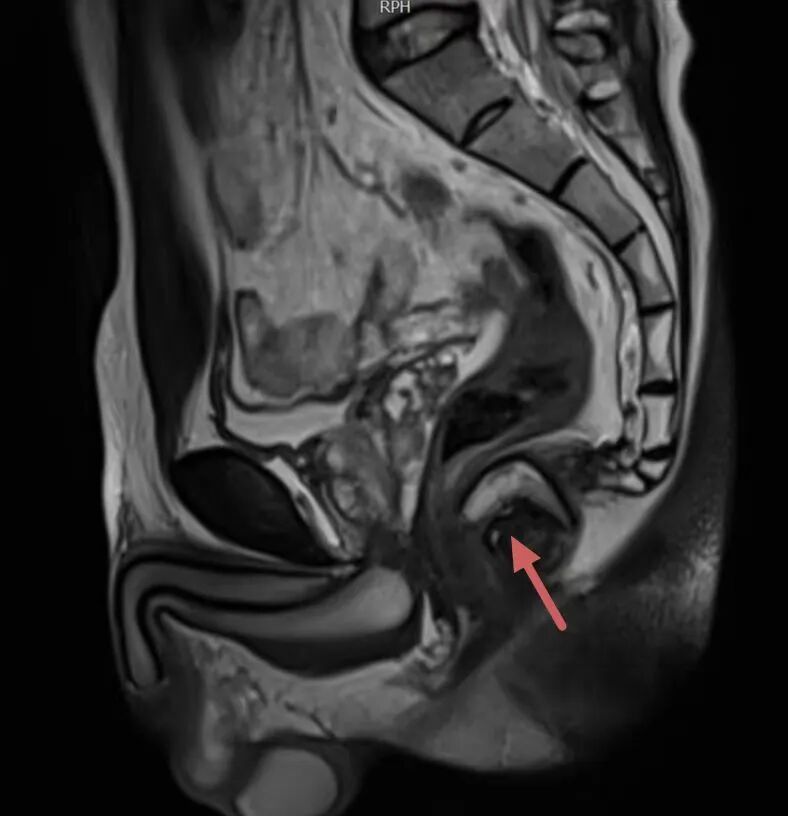

精准诊断:构建手术的“高清导航地图” 复杂性肛瘘治疗的最大难点在于瘘管走向复杂、位置深,传统检查难以看清全貌,如同在迷雾中手术,极易导致治疗不彻底或损伤肛门功能。我院肛肠科的技术突破,始于诊断环节的革新,采用 “双影像精准定位”技术,为每位复杂肛瘘患者定制手术蓝图: ·盆腔磁共振成像(MRI):已成为评估复杂性肛瘘的金标准。我院影像科与肛肠科紧密协作,针对肛瘘特点优化扫描序列。能三维立体显示瘘管的主干、分支、内口(感染源头)及其与肛门控便肌肉群的精确关系。这是制定安全、有效手术方案的基石。 · 肛周超声:则像灵活的“实时雷达”,可在术前或术中动态观察,对关键部位进行精确定位,与MRI形成完美互补。 “MRI+超声”的融合诊断模式, 为外科医生构建了覆盖术前全局规划与术中实时调整的“双保险”导航系统,确保了手术靶向的绝对精准,从源头奠定了成功的基础。 术式革新:在根治与功能保护间找到完美平衡 基于精准的影像诊断,针对吴先生这种复杂病例,肛肠科团队成功实施了“分段开窗旷置术”结合“括约肌间切开并保留括约肌挂线术”的复合术式。肛肠科刘安乐副主任医师介绍,该手术方案通过术前精准影像定位,术中先对瘘管复杂分支进行分段开窗引流,清除坏死组织,再对主瘘管采用保留括约肌挂线术,利用挂线的慢性切割作用,避免一次性切断括约肌导致肛门失禁,同时促进创面愈合。这种术式既解决了复杂瘘管引流不畅的问题,又最大程度保护了肛门括约肌功能,从根源上降低复发风险。 无痛病房建设:让康复之路温暖而从容 技术的突破不仅体现在手术室,更贯穿于围手术期的全程。市二院肛肠科着力打造的“无痛病房”是现代快速康复外科(ERAS)理念的生动实践,旨在彻底改变患者对肛肠手术“剧痛难忍”的传统恐惧。 为吴先生建立的多模式镇痛体系是一套预防性、个体化、多途径的镇痛方案: *术前预防镇痛:在手术开始前,通过疼痛教育、心理疏导联合超前镇痛药物,降低中枢神经敏感度,从源头上减轻术后疼痛。 * 术中长效麻醉:术中在手术创面区域进行药物性神经阻滞术,使术后创面无痛化持续时间达到一周以上。 *中医技术赋能:穴位贴敷、中药栓剂纳肛、肛门中药熏洗坐浴、红光照射等物理疗法,明显缓解疼痛,促进创面愈合。 在本病例中,患者术后疼痛VAS评分始终控制在3分(轻度疼痛)以下,确保了其良好的睡眠、饮食与早期下床活动。舒适的体验直接促进了康复。患者能够配合每日必要的坐浴和换药,营养摄入充足,循环呼吸功能良好,伤口在最佳状态下愈合,形成了“镇痛佳→恢复快→痛苦少”的良性循环。经过一个多月的悉心治疗与护理,张先生的创面完全愈合,肛门功能恢复正常,近期复查未发现任何复发迹象。 肛肠科通过此例多次复发的复杂性高位肛瘘的成功治愈,系统性地展示了科室在 “精准诊疗体系”与 “舒适医疗体系” 建设上的双重突破。我们将继续以此为契机,深耕肛肠疾病领域,特别是疑难复杂性肛瘘的诊疗,以更精准的刀、更温暖的术、更无痛的康复,守护每一位患者的健康与尊严。